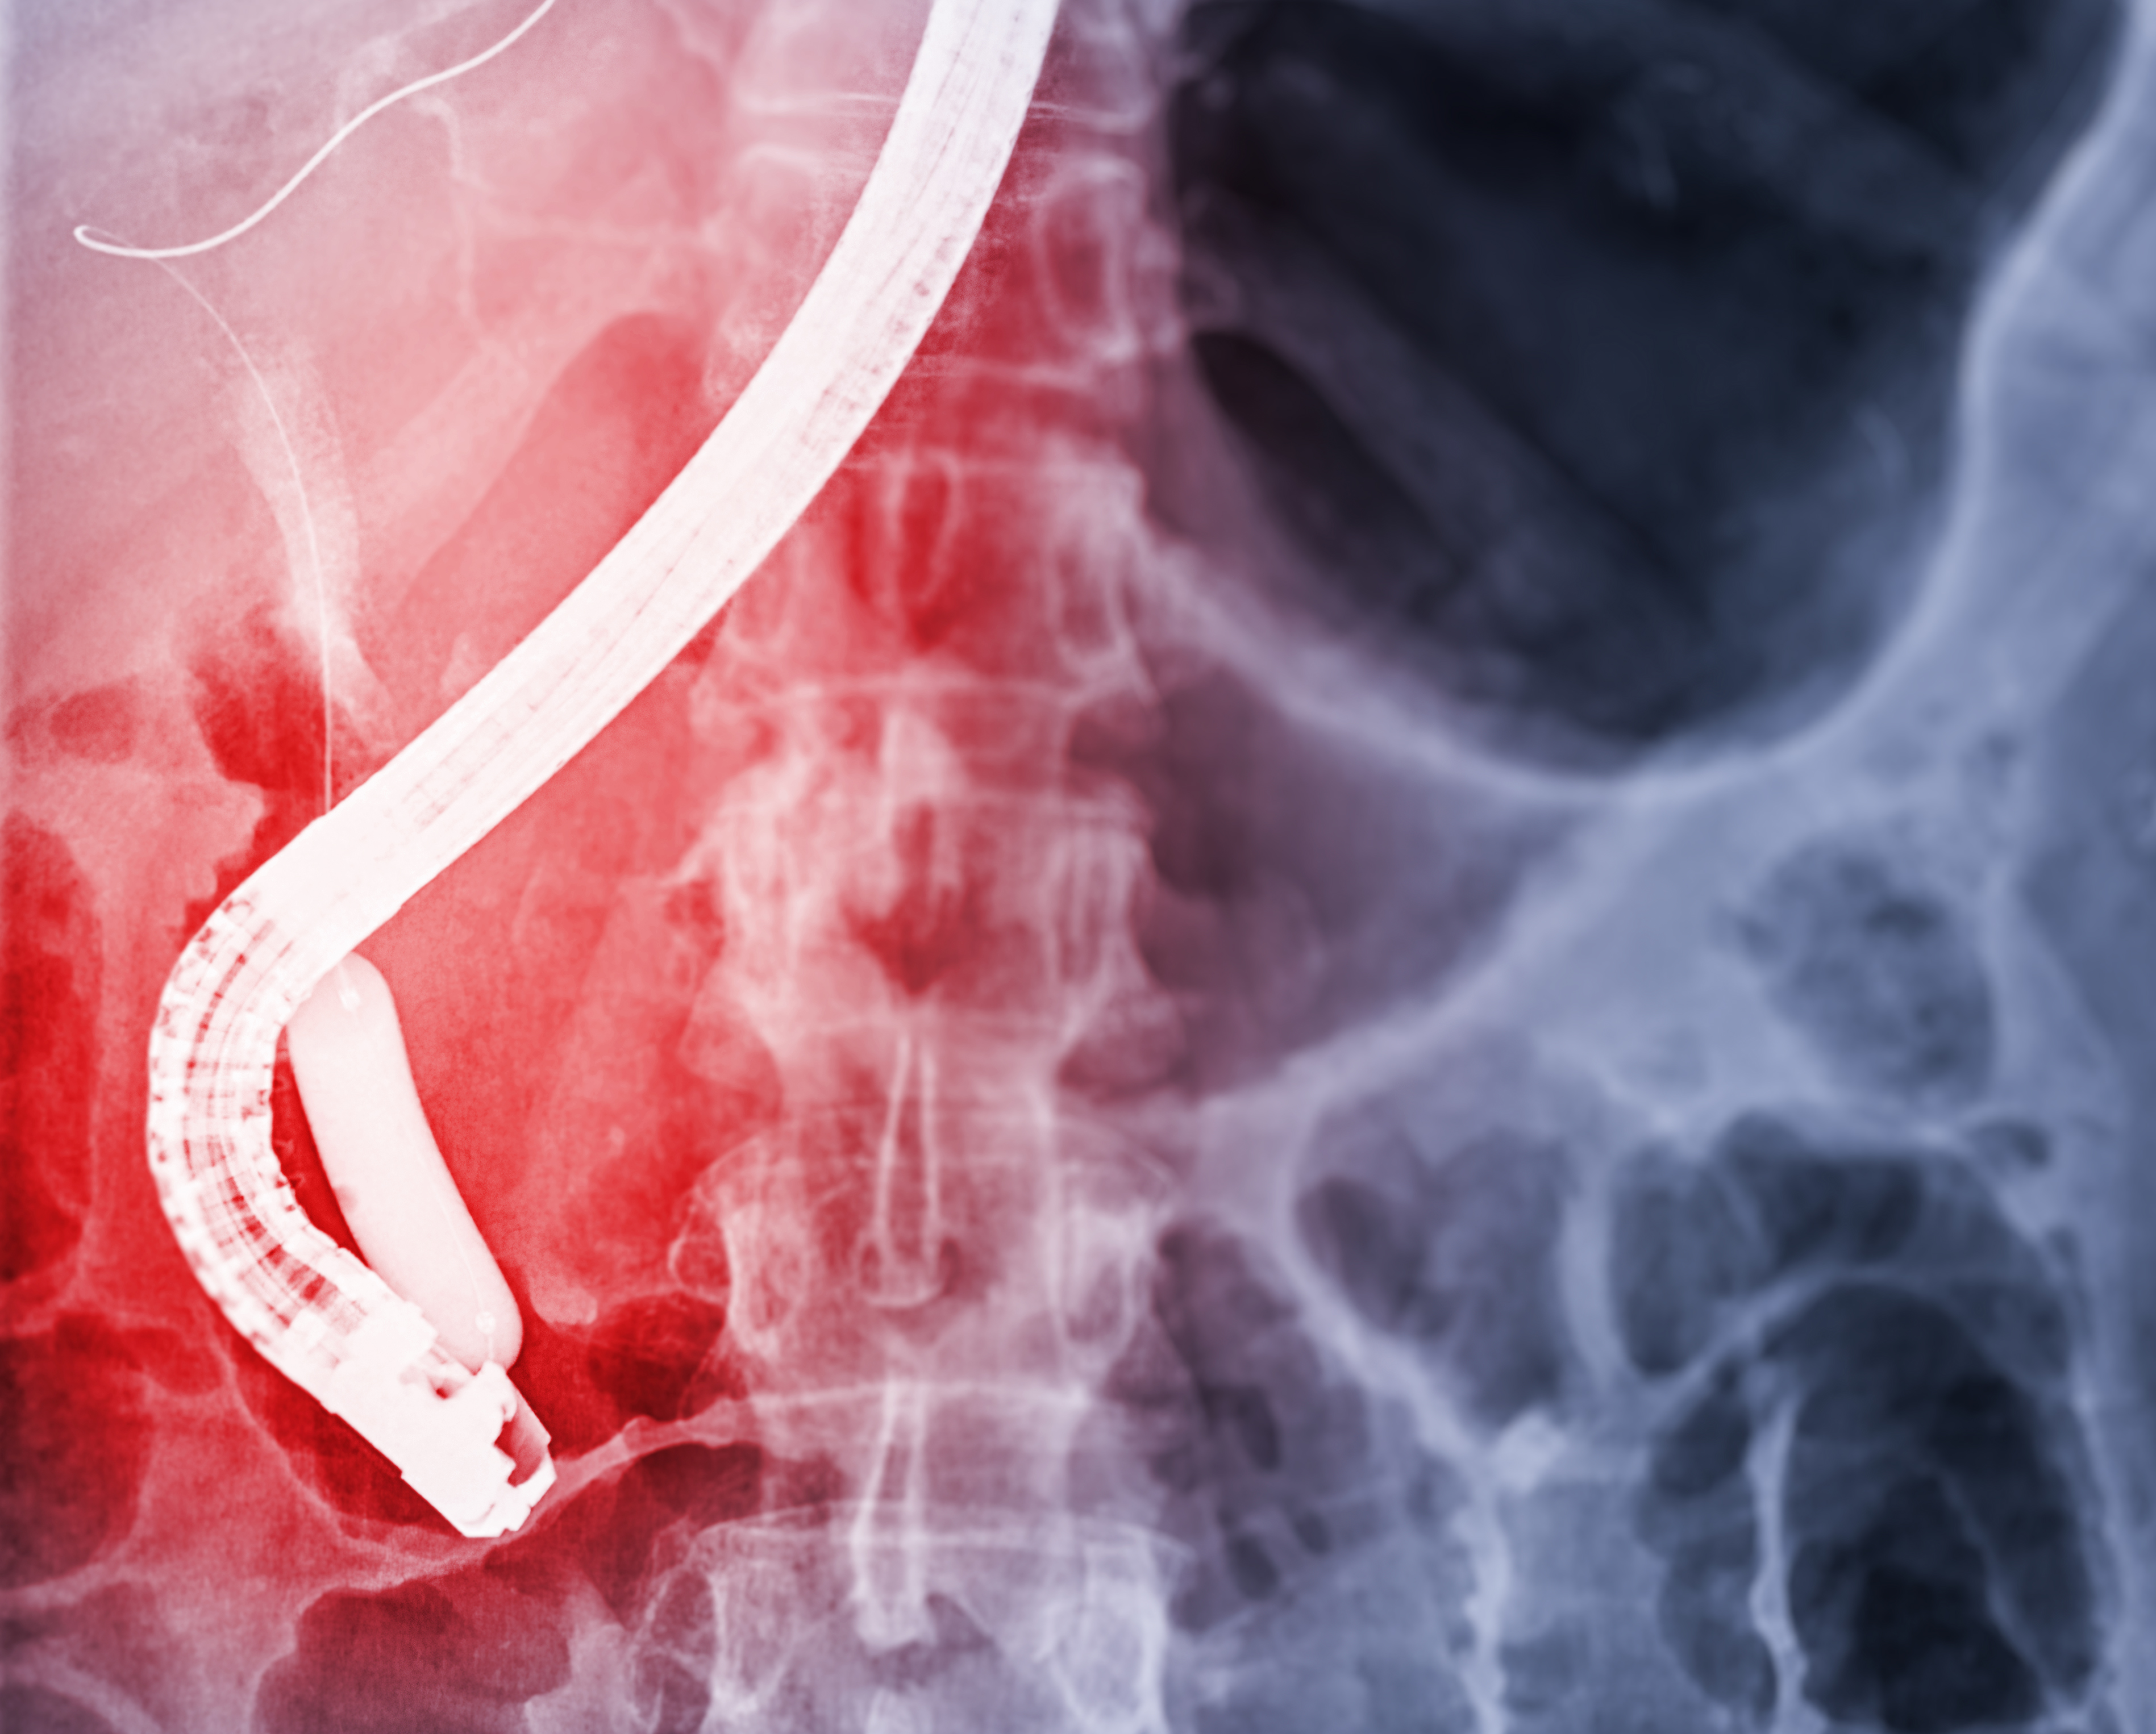

千库网_医生在现代手术室内进行 ERCP 和腹腔镜胆囊切除术后内窥镜的 X 射线图像。_摄影图编号15053027_爱奇艺.jpg

ERCP即经内镜逆行胰胆管造影术,是微创治疗胆胰疾病的主要手段之一,是将内镜经口插入十二指肠降部,经十二指肠乳头导入专用器械进入胆管或者胰管内,在X线透视下注射造影剂造影、导入子内镜/超声探头观察、进行脱落细胞/组织收集、置入胆管或胰管支架、取出胆胰管结石等操作,完成对胆、胰疾病的诊断,并在诊断基础之上实施相应介入治疗的总称。ERCP技术是胆管、胰腺疾病微创治疗的重要技术之一,被誉为“二十世纪微创外科的典范”。而内镜治疗飞速发展,目前ERCP已经从微创发展为超级微创,除了可以取出胆管结石外,还可对胆囊疾病进行相应的诊断和治疗,最大限度的保持人体器官生理结构和功能的完整性。